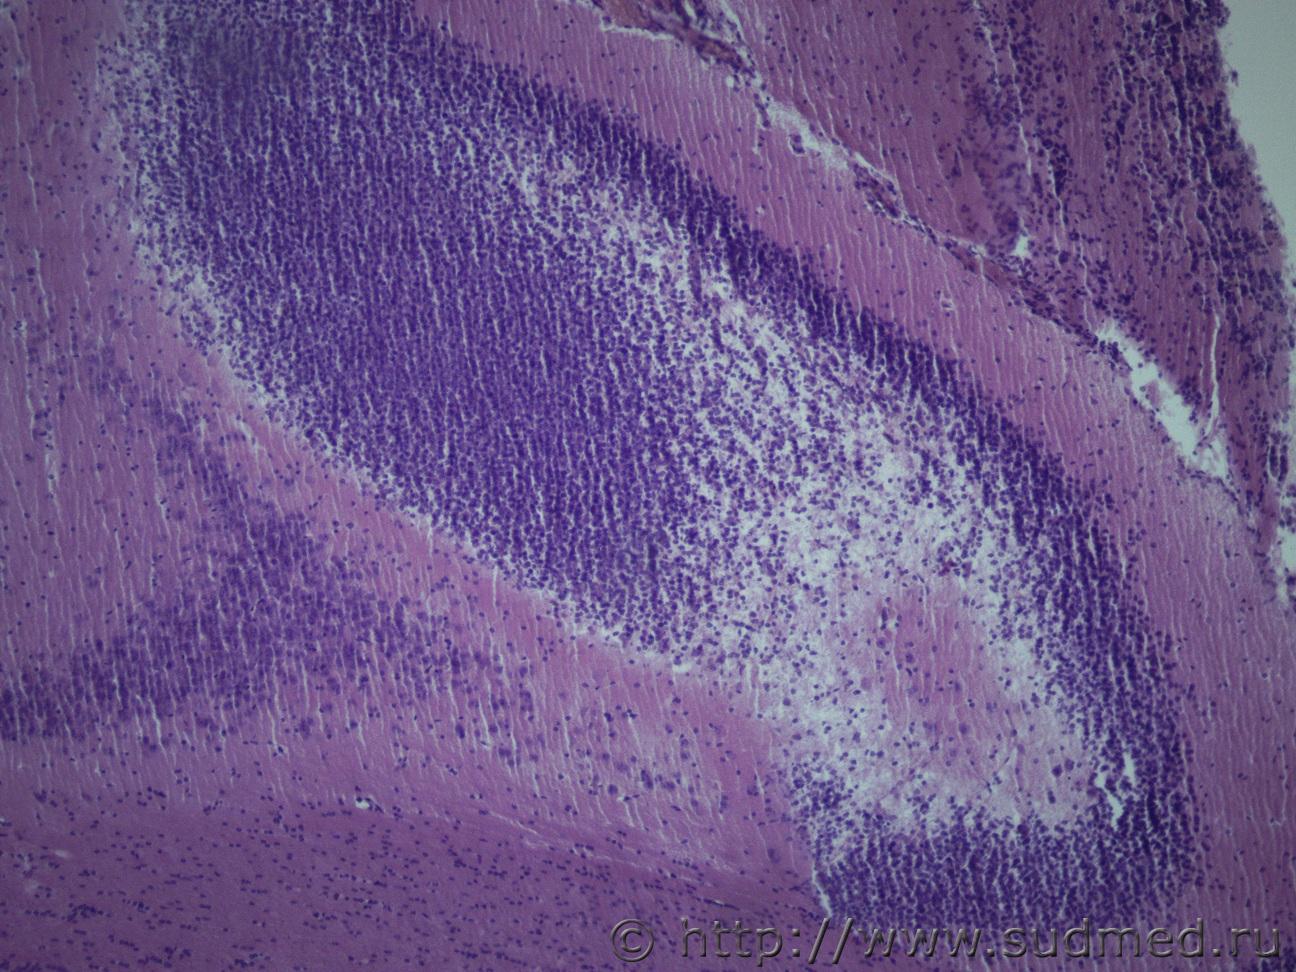

А на что это может быть похоже, в норме область гиппокампа у крыс выглядит упорядоченно и более узкой полосой. Вот такСудебная медицина - Прикрепленное изображение

А это ,скорее всего,мозжечок.

Первое фото (сообщение №1), аналогично.

Мозжечка точно не может быть, так как я его при вырезки удалила, срез проходил в средней части головного мозга через височные доли. Мозжечок у крысы выглядит вот так Судебная медицина - Прикрепленное изображение , а это поперечный срез, области гиппокампа, в норме он выглядит вот такСудебная медицина - Прикрепленное изображение ув. в обоих фото х40